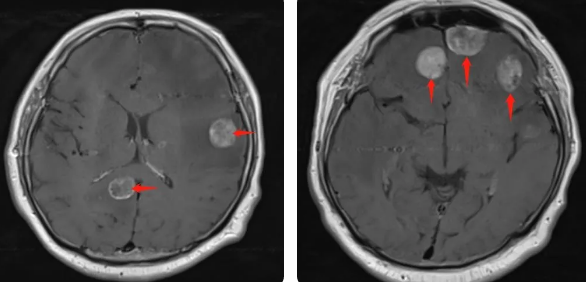

無獨(dú)有偶,60歲的左肺癌患者石先生,在外院接受了手術(shù)治療,結(jié)果術(shù)后10月出現(xiàn)腫瘤腦轉(zhuǎn)移,頭部增強(qiáng)MRI顯示:顱內(nèi)多發(fā)占位性病變伴水腫,接二連三的重?fù)糇屖壬霈F(xiàn)表情淡漠,沉默寡言,絕食等抑郁癥狀,VMAT放療技術(shù)與心理疏導(dǎo)雙管齊下,3周的治療后顱內(nèi)轉(zhuǎn)移病灶顯著縮小,部分甚至消失,困擾石先生的頭痛、頭暈癥狀也不復(fù)存在,石先生重拾對生活的希望,也對未來的治療充滿信心。